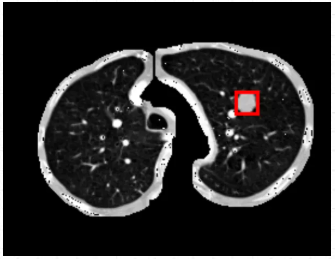

箭头指的地方可看见检测结果,可以说利用ModelArts平台训练出来的肺结节检测模型检测效果是很棒的。(直接看太小的话,可以点开图片放大看)

从最后实验的结果对比图来看,可以说利用ModelArts平台训练出来的肺结节检测模型检测效果是很棒的,虽然存在一定的肺结节病灶假阳性标记,但是这在小样本数据集的人工智能医疗检测中是会出现的情况。毕竟对于人工智能医疗检测模型来说,只用了300张标注图片就能达到这样的效果,真的让人感到惊喜。